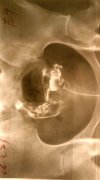

以往曾经认为细菌性阴道炎没有什么后遗症,但是现在发现它在孕妇可能会造成羊水感染、早产、产后发烧,如果做妇科手术也较易发生感染或是子宫内膜炎的现象,近年来也发现它可能与子宫颈炎或细胞变性有关。